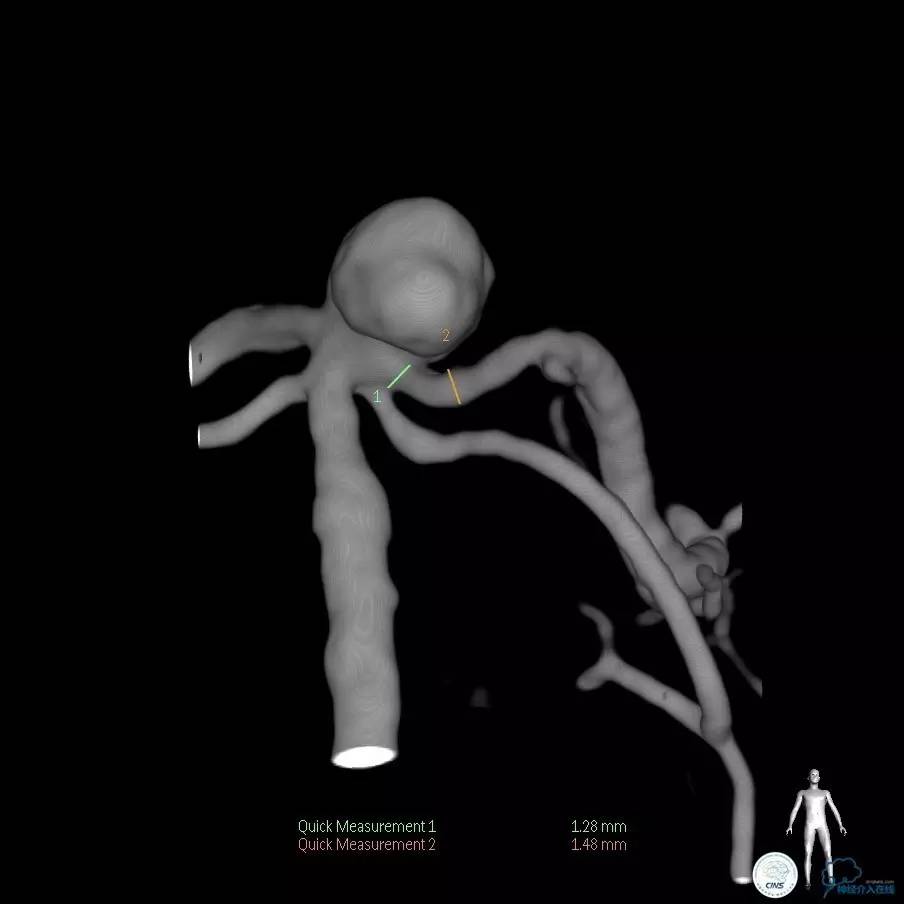

确诊:基底动脉顶端宽颈未破裂动脉瘤,动脉瘤大小约6mm×9mm,瘤颈约4毫米。

这是一例基底动脉顶端的宽颈未破裂动脉瘤,对未破裂动脉瘤治疗的主要依据就是除病人因素外,动脉瘤的大小、形态、部位是评估是否需要积极治疗的主要依据。

这个动脉瘤直径大于5毫米,位于基底动脉的顶端,形态不规则,具备破裂的高危因素。所以这个动脉瘤还是应该积极治疗。

这个动脉瘤是一个宽颈动脉瘤,动脉瘤的瘤颈和双侧的大脑后动脉关系比较密切。在进行栓塞治疗的时候要避免弹簧圈对双侧大脑后动脉以及小脑上动脉堵塞。